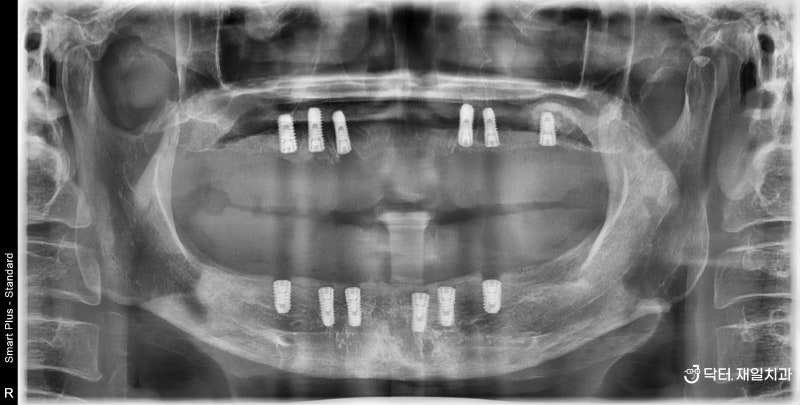

2022.09.06 / 상악 수술 후 파노라마 턱의 경우 모든 환자에게 매직4 고정 임플란트 의치용 임플란트 6개를 식립합니다. 일반 임플란트와 마찬가지로 magic4는 원할 경우 부비동 거상술과 함께 사용할 수도 있습니다. 골이식의 경우 어금니 측면 치은골이 너무 적으면 측면거상법을 이용하여 더 많은 양의 골이식재를 식립할 수 있다. 임플란트 탐색? 많은 사람들이 내비게이팅 임플란트에 대해 들어봤을 것입니다. 전체적인 경우로 보면 비용적인 요소가 있기 때문에 내비게이션 임플란트를 특별히 추천하지는 않습니다. 충분한 경험을 가진 구강외과 전문의에게 시행된다면 이러한 추가 비용 없이 성공적인 수술이 가능합니다. 일반적인 임플란트 수술과 적은 수의 보형물을 이용한 전체 임플란트 수술은 단순히 갯수로 판단하기에는 쉽지도 어렵지도 않습니다. 가능합니다~ 2022.09.06 / 상악동 수술 후 CT (상악동 설명사진 사진예시) 수술 후 CT에서 보듯이 상악동 거상은 측면거상법과 뼈이식을 이용하여 돔형태로 할 수 있습니다. 2022.10.04 / 하악 수술 후 파노라마 보통 위턱과 아래턱에 매직4 풀 임플란트 수술을 비슷한 시기에 완료하고자 하는 경우 2차 진정 후 약 한 달 후에 시행하게 됩니다. 원데이 임플란트? 원데이임플란트라는 말도 있는데 하악 골밀도가 단단한 경우에는 원데이임플란트도 가능합니다. 오후에는 PMMA를 임시치아로 사용하는데 안전을 최우선으로 하고 환자분께서 원하신다면 임시틀니로 취급하여 자연스럽게 틀니를 만들어 드립니다. 오늘 제가 말씀드리는 환자분이라면 원데이 임플란트로 수술 직후 인상채득이 가능하여 빠르게 씹을 수 있습니다. 임플란트는 하루에 한두개 심는것만큼 좋지는 않지만 전체적인 상황에서 원데이와 같은 임플란트를 하는 경우가 상당히 많습니다. . 밑면. 시간이 지남에 따라 경화됩니다. 뼈가 전혀 없는 상태에서 뼈이식을 잘하면 내 뼈가 되어 임플란트가 잘 버틸 수 있을 정도로 튼튼해집니다. 신비로움이 느껴지고 인체가 정상인 것 같습니다. 아무것도 아닌 것 같은 느낌? ㅎㅎ 2023.02.10 / 완전치료 파노라마매직4 전체 임플란트 치료기간 일반적으로 발치 후 즉시 식립을 하는 경우 총 증례 수는 모두 4~5개월 정도의 기간을 고려하는 것이 가장 좋습니다. 임플란트 부작용 예방 임플란트 부작용 관리 임플란트주위염! 관리가 잘못되었을 때 발생할 수 있습니다. 그렇더라도 초기에 예방할 수 있도록 정기적인 검진을 통해 잘 확인하는 과정이 필요합니다. 오늘은 저희 무치악임플란트/전악임플란트/전악임플란트/수면마취가 많은 길동임플란트/성내동임플란트가 좋은곳 제일치과의 고정임플란트틀니 매직4 치아를 건강하게 지켜주고 잘먹게 해주는 두려운 분들은 치과진료, 진정치과의원에서 치과 수면치료로 편안한 경험을 하실 수 있으며, 이후 사랑니 등을 과감하게 뽑을 수 있도록 도와드립니다. 치과에서 행하는 모든 치료가 가능합니다. 이것으로 닥터자일리톨의 두 번째 이야기를 마칩니다! 건강하고 행복한 하루 되세요~ 강동구 올림픽로 796 제일치과의원 강동구 2층